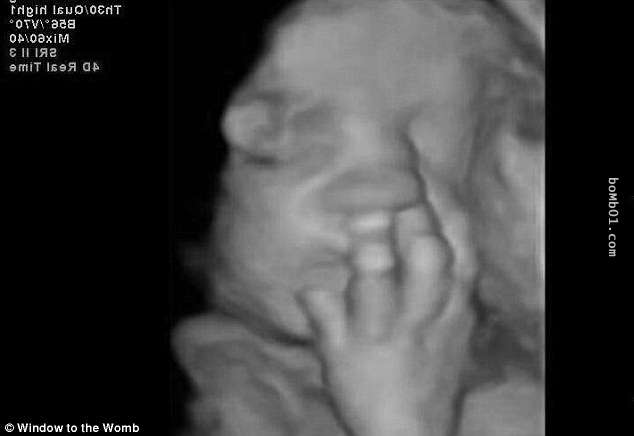

▼這個寶寶手腳並用,擋住了自己的臉。